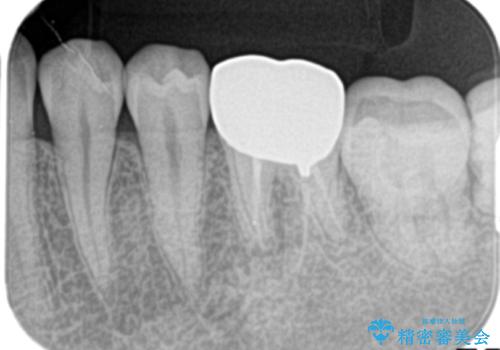

- 下の奥歯の銀歯を白くしたいとのことで来院されました。

痛みなどの症状はなく、前に根管治療を行っている歯になります。

古い銀歯を除去し、審美性の良いセラミッククラウンでの治療を行うこととしました。